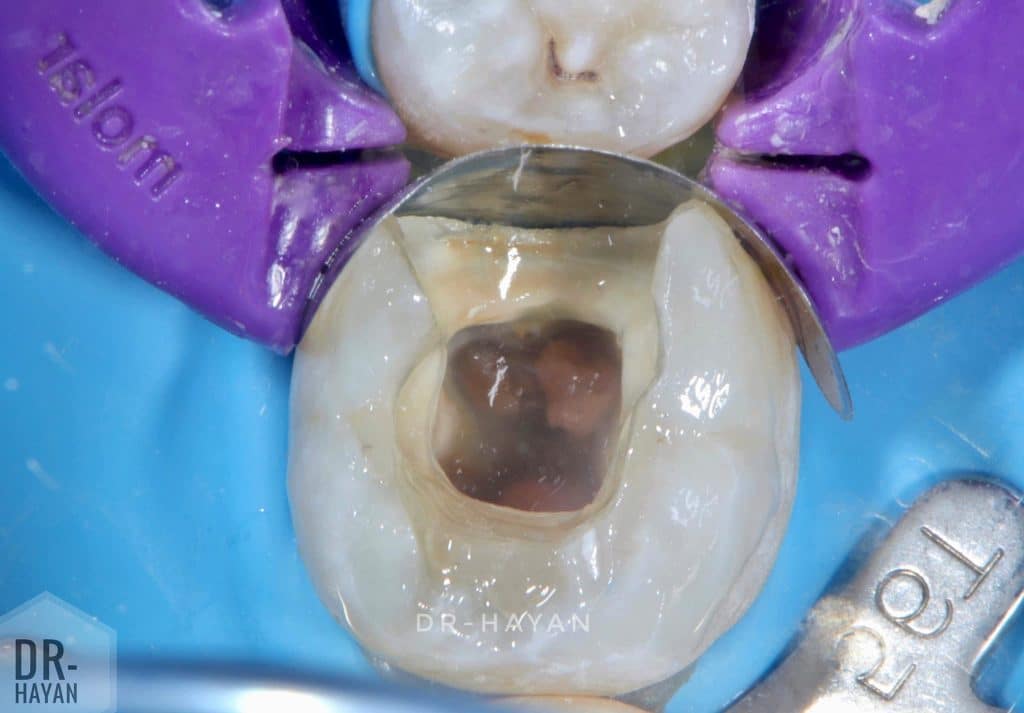

Initial view

Isolation first then disinfectant the the tooth

Access and pus drainage